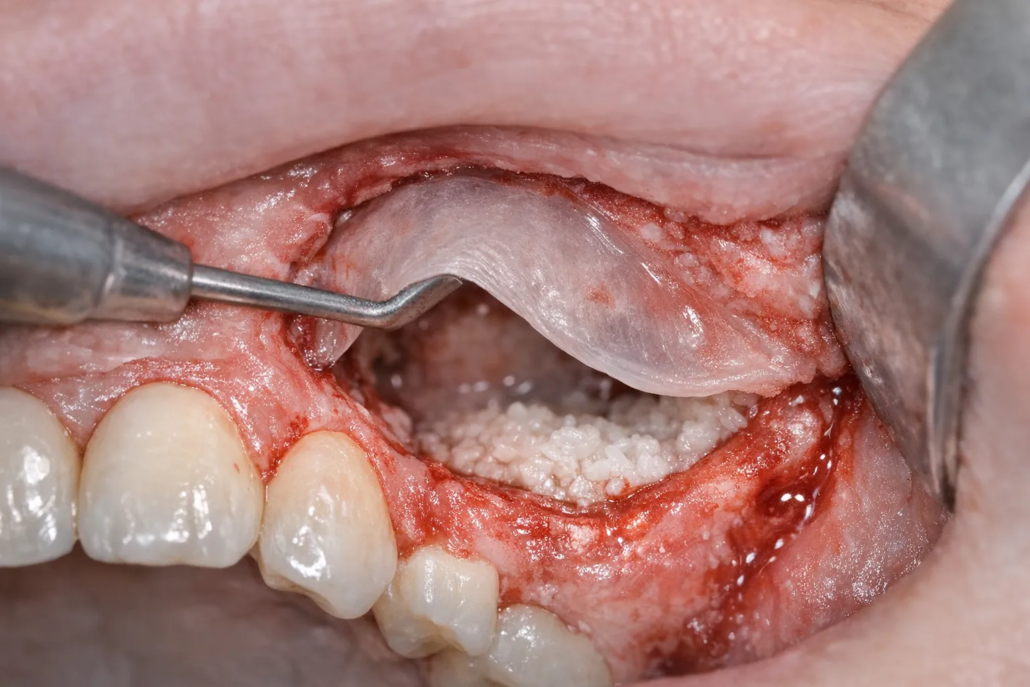

Greffe osseuse dentaire : douleur combien de temps ? (timeline + conseils)

Après une greffe osseuse dentaire, la question la plus fréquente est simple : combien de temps vais-je avoir mal ? Dans la majorité des cas, la douleur est modérée, bien contrôlée par les antalgiques, et elle diminue nettement au bout de quelques jours. En revanche, la cicatrisation de l’os prend beaucoup plus longtemps (plusieurs mois), même si vous vous sentez “réparé” rapidement.

Combien de temps dure la douleur après une greffe osseuse dentaire ?